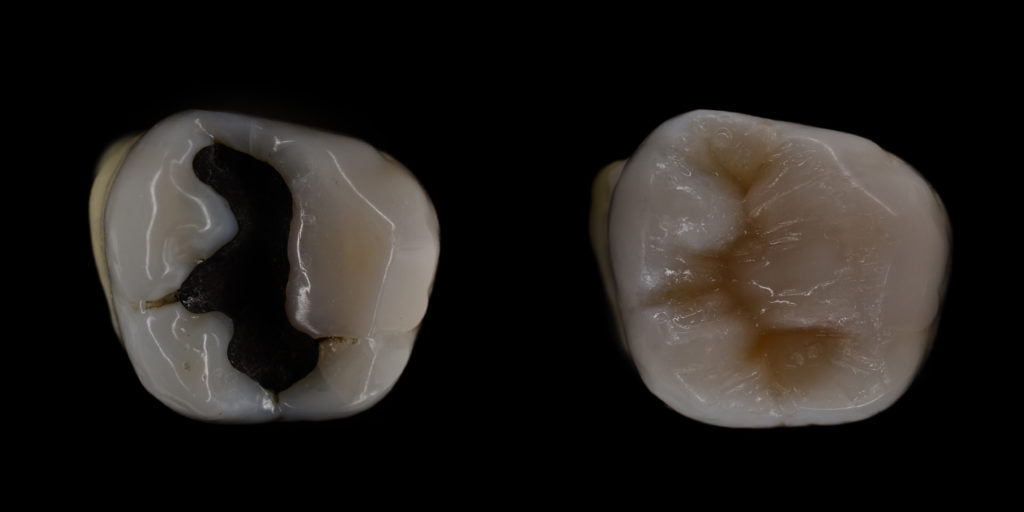

What are amalgam fillings?

Also known as “silver fillings” or “mercury fillings”, dental amalgam is a mixture of various metals. These metals are mercury, silver, tin and copper. Approximately 50% of the amalgam is comprised of mercury. The mercury binds the metals together to enhance the strength and durability of the amalgam. It should be noted that when mercury is combined with the other metals it forms a safe and stable compound, which has been in use over the last 150 years!

Due to its effectiveness and cost, amalgam is still the restorative material of choice in certain parts of the world. In recent times, however, there have been concerns over the use of amalgam restorations (fillings), relating to the mercury release in the body and the environmental impact following its disposal. Resin composites have become an aesthetic alternative to amalgam restorations and there has been a remarkable improvement of its mechanical properties to restore posterior teeth.

Amalgam filling

1. Unsightly: generally amalgam fillings are easy to spot even if you aren’t a dentist!

3. Limited support in large cavities: not as supportive when dealing with large cavities as has no bonding properties to the tooth, instead it is held by compression. This can lead to fractures of the tooth over time.

4. Amalgam tattoo: amalgams that have been in the mouth for many years can leave a dark tattoo in the area of the gum or cheek that is in contact with it.